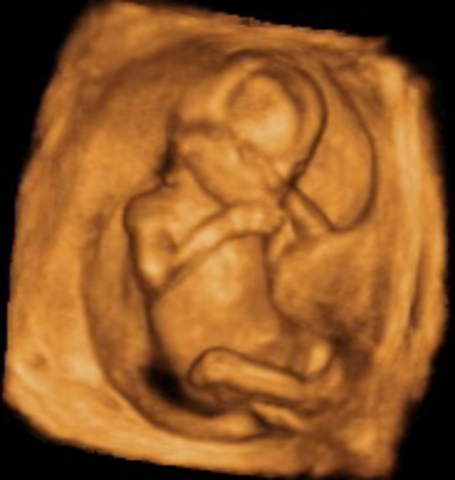

El embrión se denomina feto en lo sucesivo, la movilidad es mucho mayor e incluye movimientos corporales y de los 4 miembros; se mueve por todo el saco gestacional lleno de líquido amniótico. Las neuronas siguen multiplicándose de manera muy rápida. Los órganos esenciales del bebé ya se han formado y el feto se hace más resistente a las lesiones externas

• Semana 11

Semana 11

Los órganos y estructuras cada vez son más grandes y fáciles de visualizar, los riñones comienzan a producir orina y la vejiga se plenifica, el estómago es fácilmente visible. El estudio del sistema nervioso central es muy interesante e importante, se pueden ver los ventrículos, el cerebelo y la hoz cerebral con gran detalle, la corteza cerebral es muy fina y transparente al ultrasonido